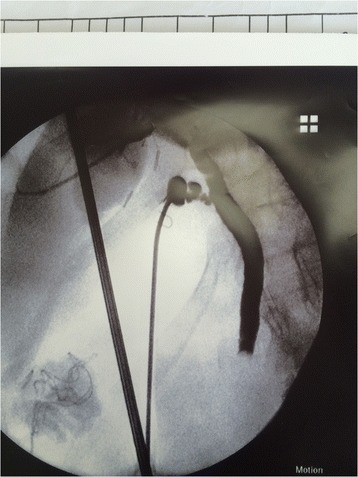

Choledochotomy approach (26 patients)

This approach was used either after failed trial of cannulation of cystic duct or failed stone extraction through cystic duct, in three patients, we employed it without trying the trans-cystic technique because they were post failed ERCP due to big impacted stones. IOC was done through CBD puncture with lumber needle which showed CBD stones. In these cases we converted to choledochotomy in which the CBD was exposed and a vertical ductotomy was done on the anterior surface of the duct below the junction between cystic duct and CBD (Fig. 3). The techniques for stone clearance are identical to the trans-cystic approach. Through the choledochoscope, flushing with saline was done under pressure to facilitate clearance of small stones. Dormia basket and/or balloon catheter can be also used to pull stones to the abdominal cavity then to be retrieved outside (Fig. 4). The choledochotomy was closed over a T-tube in nine cases and over an antegrade stent in 10 cases; the stent was inserted through the site of cholodotomy under guidance of fluoroscopy for removal by ERCP later. Primary closure of the CBD was done in the remaining seven patients with absorbable suture. External tube drains were used only when we perform choledochotomy technique and not used in trans-cystic technique.